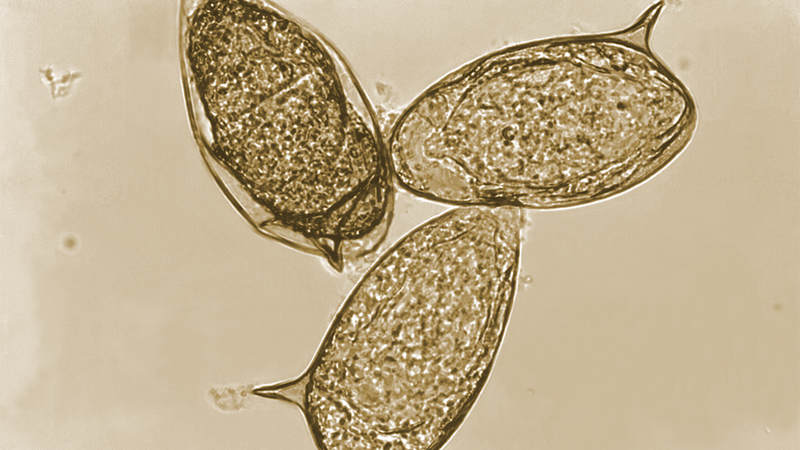

Đối với mẫu phân, tại phòng xét nghiệm, kỹ thuật viên sẽ tiến hành xử lý mẫu và chuẩn bị tiêu bản bằng cách nhỏ dung dịch nước muối sinh lý và dung dịch Lugol lên lam kính, sau đó soi tươi trực tiếp dưới kính hiển vi quang học nhằm tìm kiếm hình ảnh trứng sán trong mẫu bệnh phẩm. Phương pháp này cho phép quan sát rõ đặc điểm hình thái của trứng sán máng, từ đó hỗ trợ chẩn đoán xác định bệnh.

Đối với mẫu nước tiểu, mẫu sẽ được ly tâm để thu phần cặn, sau đó phần cặn này được cho vào môi trường nước ấm. Nếu trong mẫu có trứng sán, sau vài giờ trứng sẽ nở thành ấu trùng lông (miracidium). Khi soi dưới kính hiển vi với độ phóng đại x10 hoặc x40, có thể quan sát thấy ấu trùng di chuyển rõ rệt, đây là dấu hiệu có giá trị trong chẩn đoán sán máng đường tiết niệu.